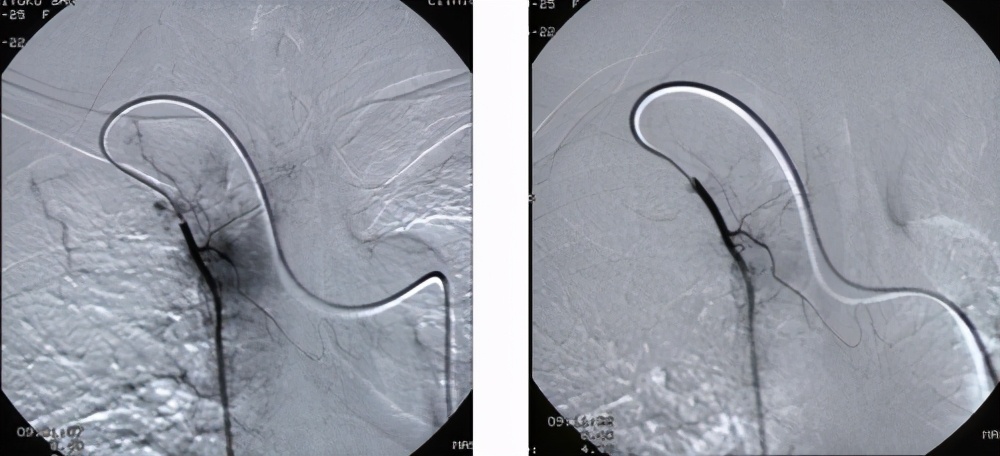

病例:乳腺癌骨转移

A治疗前DSA造影见胸骨区瘤染色BCMI化疗药物治疗后立刻造影见瘤染色明显减轻